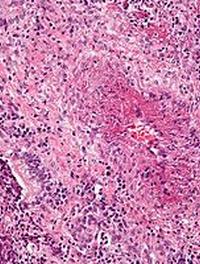

La VAA (Vascularite Associée aux Anticorps anti-neutrophiles cytoplasmiques ou ANCA) est un groupe de maladies auto-immunes graves, [...]